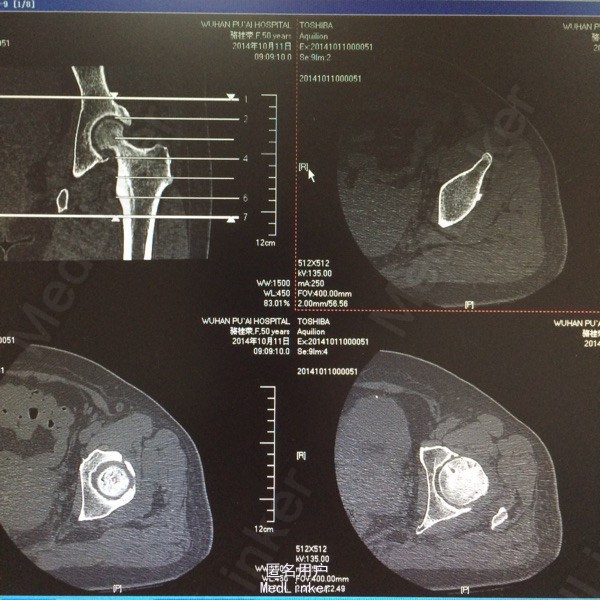

患者,女,50岁。因“双髋关节疼痛活动受限一年余”入院。 患者一年余前无明显诱因感双髋关节疼痛,活动后症状加重,休息后稍有缓解,不伴发热、咳嗽,否认明确外伤史。于今年8月在我院门诊拍片(M00085020)示:双侧股骨缺血性坏死。今为求进一步治疗来我院求诊,门诊查体阅片后以“双侧股骨头缺血性坏死”收住我科。 自起病以来,患者饮食睡眠可,二便正常,体力下降,体重无明显改变。 既往:否认肝肾病史,否认食物、药物过敏史

体格检查:T 36.8℃ P 78次/分 R 20 次/分 BP 142/96mmHg,神志清醒,平静面容,扶拐跛行步入病房,查体合作。发育正常,全身皮肤未见黄染,浅表淋巴结未及肿大,头颅无畸形,双侧瞳孔等大等圆,光反射灵敏。颈软,胸廓无畸形,双肺呼吸音清晰,未闻及干湿性啰音。心律齐,各瓣膜听诊区无杂音。腹平软,无压痛反跳痛,脊柱无畸形,各棘突无压痛。双上肢正常。 专科情况:双髋关节未见明显肿胀,腹股沟中点处深压痛,下肢无轴向叩击痛,双髋关节活动度因疼痛减小,4字征阳性,双足背动脉搏动可及,各趾感觉、活动正常,直腿抬高试验阴性,双下肢无明显短缩。 门诊资料:我院MRI(M00085020)示:“双侧股骨头缺血性坏死”。

初步诊断:双侧股骨头缺血性坏死 鉴别诊断:X线片上未见骨肿瘤,骨囊肿等征象可与肿瘤相相鉴别,具体有待于进一步检查。 诊疗计划:1.卧床休息,暂不负重,对症支持处理。 2.完善相关检查(血、尿分析、肝肾功能、骨盆平片、髋关节CT、胸片ECG、心脏彩超等)。 3.择期手术治疗(髋关节置换术)。